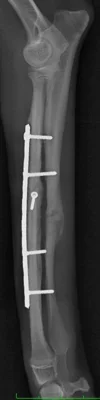

固定強度は右前肢のが強く、跛行の回復も早いはずですが、

このイタグレさんは手術直後から左前肢をより使ってました。

この段階でもしっかり負重し、歩いています。

左前肢を右より先に積極的に負重する事は想定外でした。

もう少し強度を高めておけば、よりこの時点でもより

仮骨形成を認めたと思われます。

治療経過はレントゲンだけで判断できません。

順調に足への負荷が増えていることも大切です。

中和プレート単独では固定強度が足りないため、術後早期は外固定を併用します。

初期固定は強めに、経過とともに不安定化(destabilization)させていきます。

インプラントの強度が強い方が術者としては安心かもしれませんが、

強度が強すぎると骨が育ちません、

弱すぎれば仮骨は出ますが破綻するリスクを伴います。

適切な強度のインプラントを選択する事が大切です。